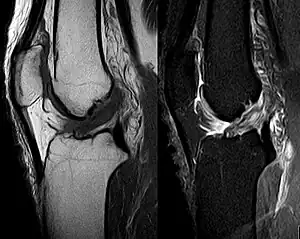

Medical imaging

Though clinical examination in experienced hands can be accurate, the diagnosis is usually confirmed by magnetic resonance imaging, which provides images of the soft tissues like ligaments and cartilage around the knee.[1] It may also permit visualization of other structures which may have been coincidentally involved, such as the menisci or collateral ligaments.[30] An x-ray may be performed in addition to evaluate whether one of the bones in the knee joint was broken during the injury.[9]

MRI is perhaps the most used technique for diagnosing the state of the ACL, but it is not always the most reliable technique as the ACL can be obscured by blood that fills the joint after an injury.[31]

MRI is particularly useful in cases of partial tear of the ACL. The anteromedial band is most commonly injured compared to the posterolateral band.[32]